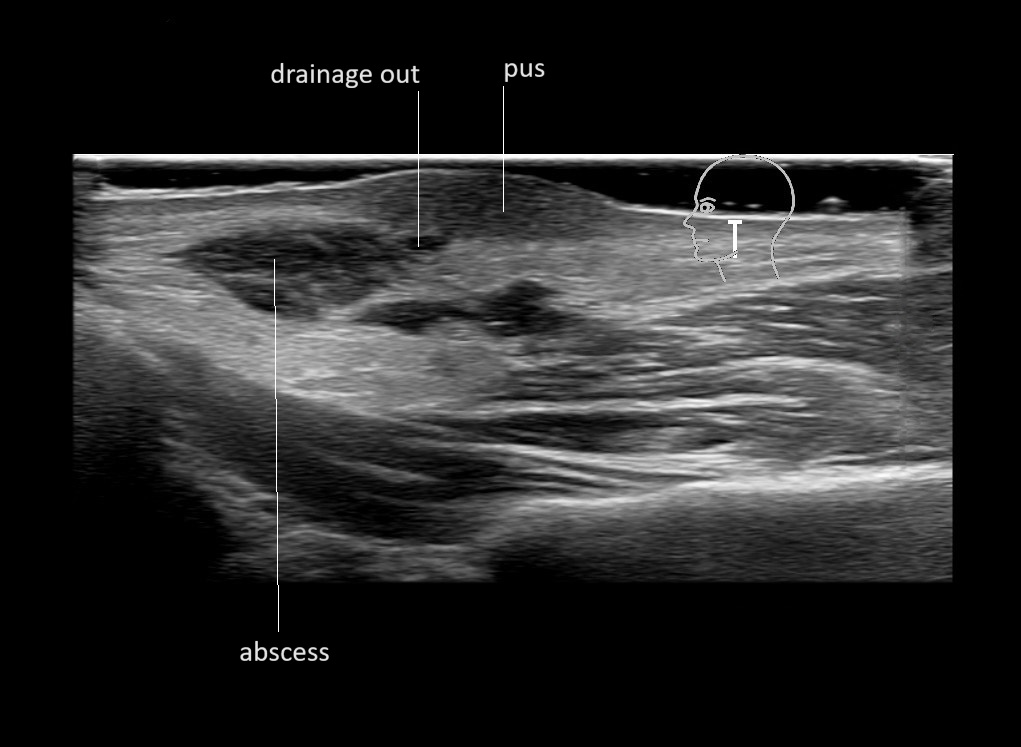

With ultrasound signs of inflammation can be visualized. Edema can be seen as a hyperechoic appearance of the subcutaneous fat, sometimes separated by hypoechoic fluid filled area’s, known as cobblestone appearance. Increased vascularization (hypervascularity) can be seen on colour Doppler. An abscess will appear as a fluid collection appearing as an irregular hypoechoic area with heterogeneous internal echoes and a thickened wall. Posterior acoustic enhancement can be present, and there is vascularity around but not within the mass. Under ultrasound guidance, abscesses can be managed by needle aspirations (18G) under antibiotic cover.